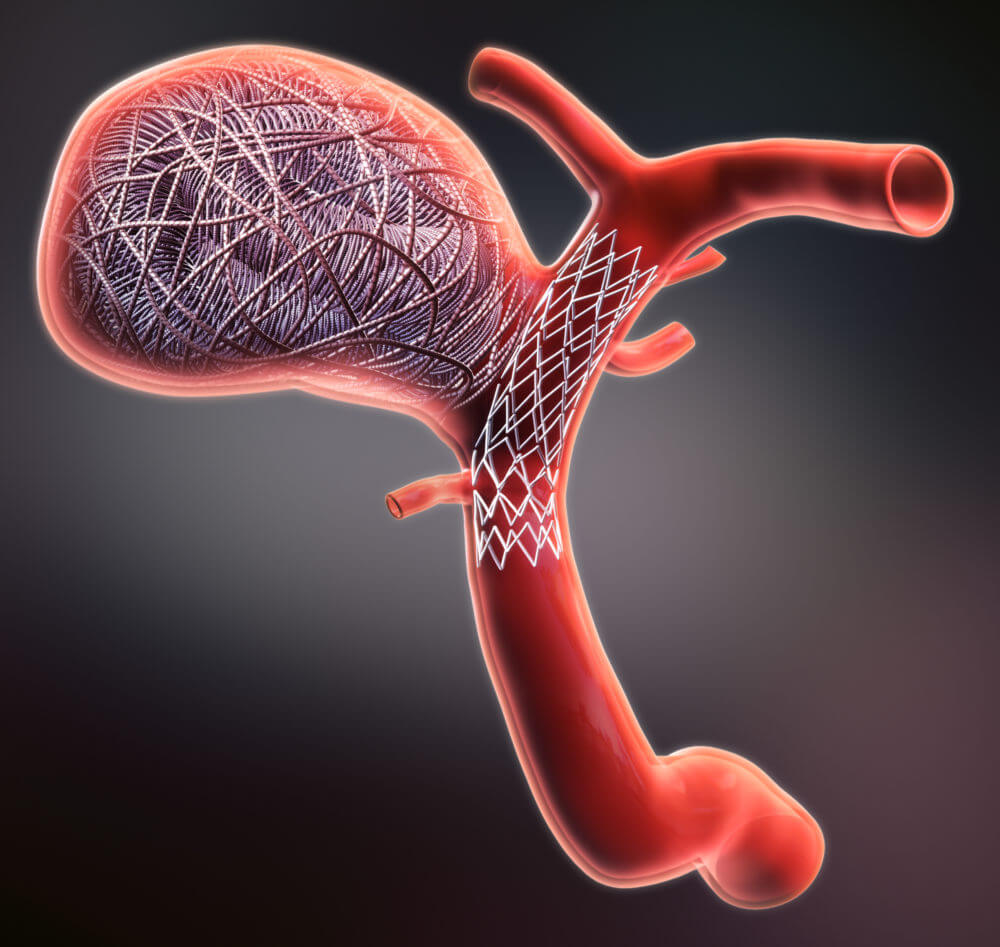

Снимки и иллюстрации микроаневризм сосудов головного мозга